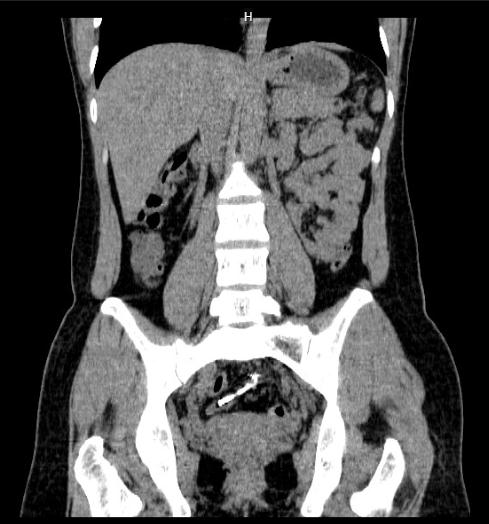

Khoa Phẫu Thuật Tiêu hóa – Gan mật tụy vừa điều trị phẫu thuật một trường hợp vòng tránh thai đâm xuyên thành tử cung vào thành đại tràng Sigma sau ba năm đặt vòng. Đó là trường hợp chị H.H.L (38 tuổi) vào viện vì đau bụng vùng chậu dưới rốn âm ỉ, kèm đi ngoài ra máu. Chị L có tiền sử đặt dụng cụ tránh thai cách 3 năm và không đi kiểm tra lại. Sau khi hỏi bệnh, thăm khám và làm các xét nghiệm cần thiết, soi đại tràng và chụp cắt lớp vi tính, cho thấy hình ảnh dụng cụ tử cung nằm 1 đầu ở trong lòng đại tràng sigma, 1 đầu nằm chặt trong thành của đại tràng sigma phía bờ mạc treo. Với vị trí này, bác sĩ không thể lấy dụng cụ tử cung qua đường nội soi ống mềm do có thể gây thủng đại tràng vào ổ bụng làm nặng thêm cho người bệnh. Vì vậy, các bác sĩ quyết định phẫu thuật để lấy dụng cụ tử cung lạc chỗ và xử lý chỗ thủng đại tràng. Phẫu thuật nội soi hoàn toàn là phương pháp được lựa chọn vì là phương pháp ít xâm lấn nhất cho người bệnh

Dụng cụ tử cung trong thành đại tràng sigma qua nội soi đại tràng và phim CLVT